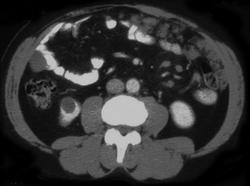

Virtual Colonoscopy With Volume Rendering